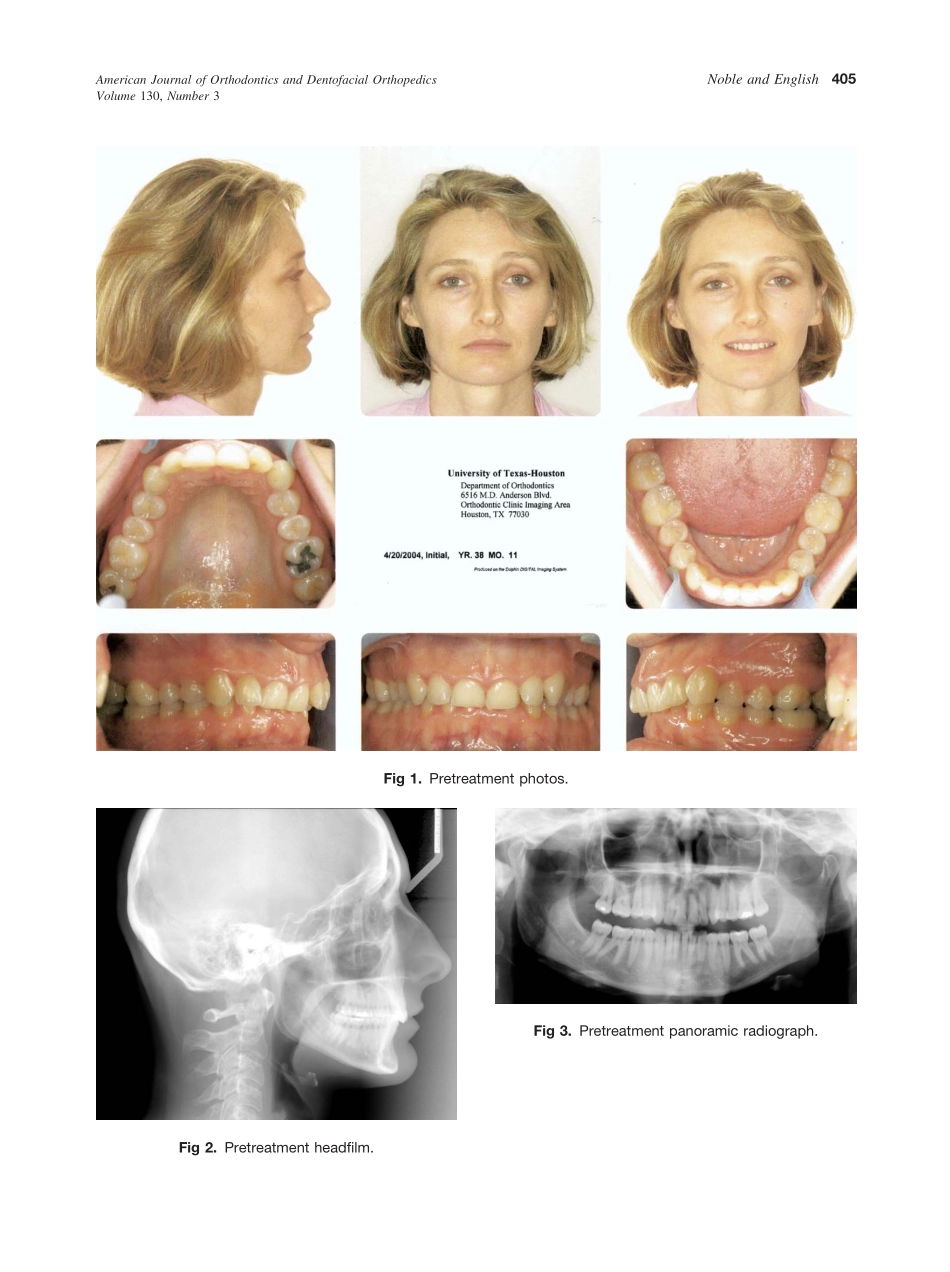

ABOCASEREPORTCategory7:AnteroposteriorskeletaldiscrepencyReagonNobleandJerylEnglishHouston,TexThiscasereportwaspartofadisplayofcasessponsoredbytheAmericanBoardofOrthodonticsattheAAOannualsessioninS...